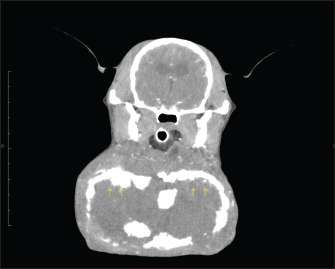

A computerized tomography (CT) performed on day 8 showed a hyper-absorbable area comparable to cortical bone lining the entire mass wall. In the arterial phase, the interior of the hyper-absorbable area was occupied by a slightly hypo-absorbable area compared to the margins of the mass lesion (Fig. 3). There was no vascular run inside the mass, and the mandibular glands, sublingual glands, and mandibular lymph nodes were enlarged bilaterally. There were no significant findings in the mandible.

Fig. 3. CT scan on day 8. A hyper-absorptive area as large as the cortical bone was observed lining the entire mass wall (arrow). In the arterial phase, the interior of the highly absorbable area was occupied by a slightly less absorbable area compared to the margins of the mass lesion.